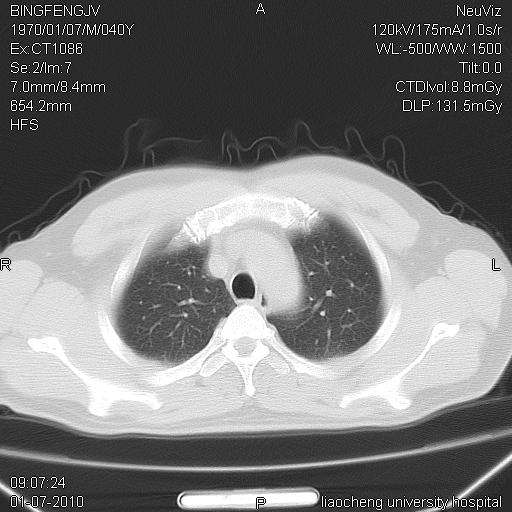

标题: CT23764B:男 40 肺部CT [打印本页]

标题: CT23764B:男 40 肺部CT

治疗2周后

炎症性病灶,继发性改变。

考虑左肺上叶近胸膜下炎症并肺气囊形成。

炎症,大部吸收。